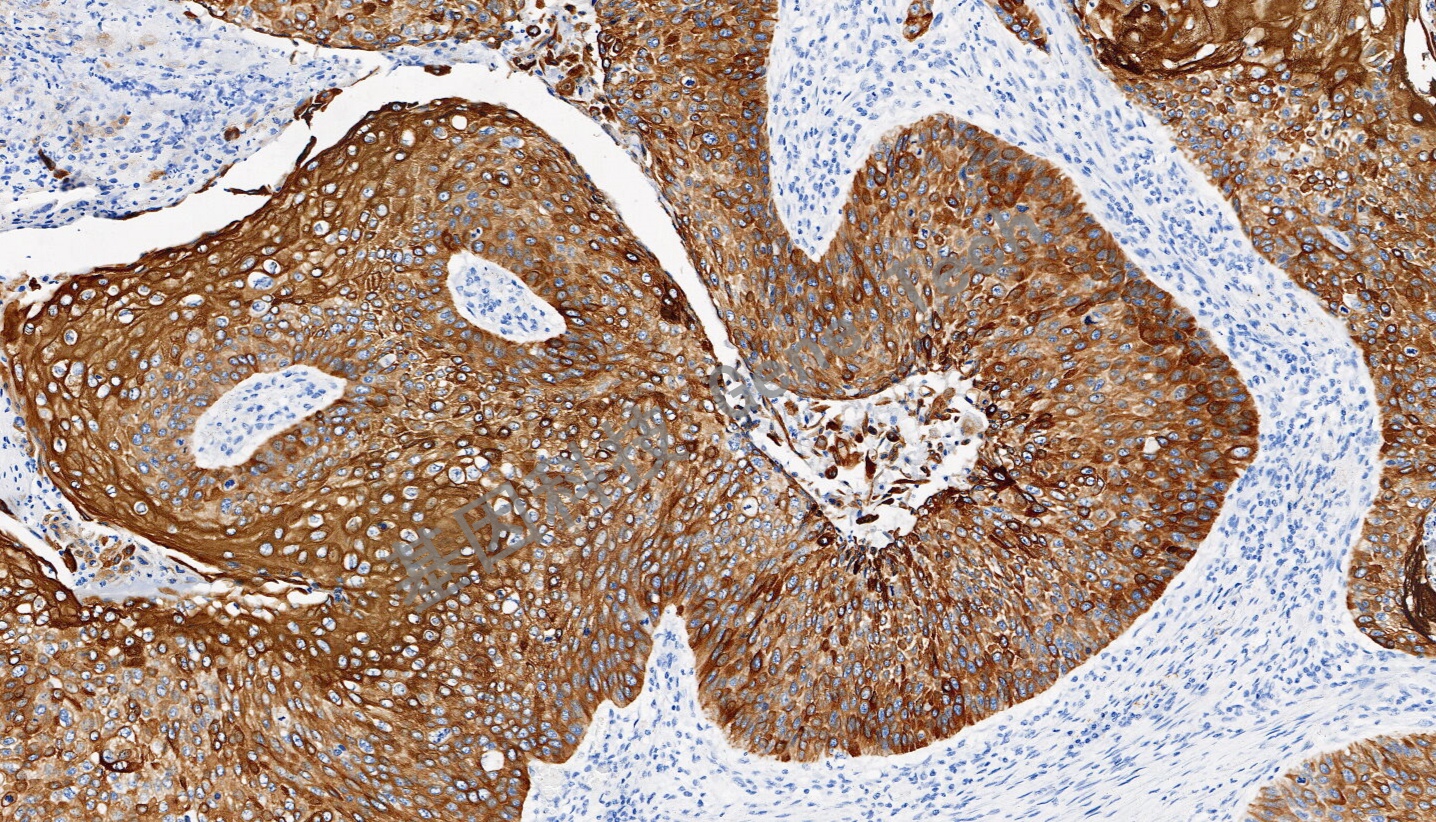

CK6 兔抗人 細胞角蛋白 6(CK6)抗體試劑(免疫組織化學法)

| 預處理:高pH熱修復 | 陽性部位:細胞漿 | 陽性對照:食管癌 |

| 簡介:細胞角蛋白6(CK6)是一種上皮特異性的II型角蛋白,通常與創(chuàng)傷后的角質(zhì)細胞活化相關,因此也被認為是一類愈合因子。CK6總是與I型角蛋白CK16和/或CK17成對出現(xiàn),通常在尚未角質(zhì)化的上皮組織的基底層細胞中表達,如口腔粘膜、食道、舌乳頭,在毛囊外根鞘中也有明顯表達。在腫瘤組織中,CK6在多數(shù)的鱗狀上皮癌中表達,特別是在鱗癌癌巢的中間成熟細胞層。CK6通常與CK5一起配套用于鱗癌與腺癌、間皮瘤與腺癌的鑒別診斷,也可用于導管上皮惡性增生的鑒別。 | ||

| 食道癌石蠟切片,用 CK6(GT2490)染色,細胞漿陽性,DAB 顯色。 | ||